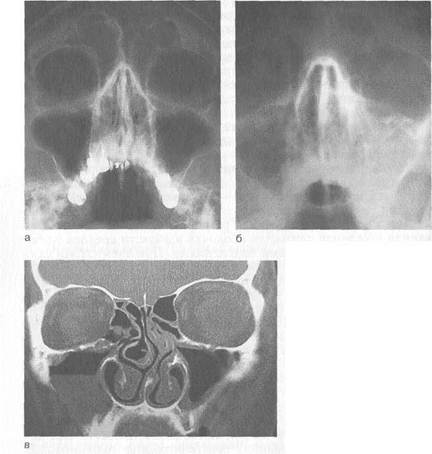

Рис. 2.29. Гнойный правосторонний фронтит.

а _ обзорная рентгенограмма; б — компьютерная томограмма.

Диагностика. Она не представляет трудностей и основана на данных анамнеза, характерных жалобах больного, результатах клинического и инструментального осмотра, эндоскопического и рентгенологического исследований (при необходимости с введением контрастных препаратов), данных КТ (рис. 2.29).